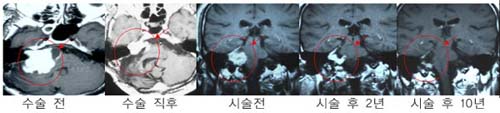

û½Å°æÁ¾¾ç

¿ìÃø

û½Å°æÁ¾¾ç ȯÀÚÀÇ MRI »çÁø. °¨¸¶³ªÀÌÇÁ

¹æ»ç¼±¼ö¼ú 4³â ÈÄ Á¾¾çÀÇ Å©±â°¡ ÇöÀúÈ÷

°¨¼ÒÇÏ¿´À¸¸ç ½Ã¼ú ÈÄ 10³â° ¸ðµÎ ¿ÏÄ¡µÇ¾ú´Ù.

Å©±â°¡

Å« ¾ç¼ºÁ¾¾ç(û½Å°æÁ¾¾ç)ÀÇ °æ¿ì ¼ö¼úÀû

Ä¡·á·Î¼ ¿ÏÀüÀûÃâÀÌ µÇÁö ¾ÊÀº ³²Àº Á¾¾ç¿¡

°¨¸¶³ªÀÌÇÁ ¹æ»ç¼± ¼ö¼úÀ» ½ÃÇàÇÏ¿© ¿ÏÄ¡µÊ